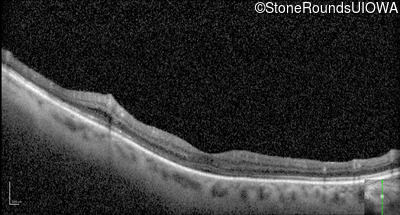

Optical Coherence Tomography - Left - 20/50 +3

Exemplar / OCT Stack

OCT Stack